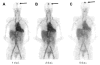

Increased human epidermal growth factor receptor 2 (HER2) expression is a hallmark of aggressive breast cancer. Imaging modalities have the potential to diagnose HER2-positive breast cancer and detect distant metastases. The heterogeneity of HER2 expression between primary and metastatic disease sites limits the value of tumor biopsies. Molecular imaging is a noninvasive tool to assess HER2-positive primary lesions and metastases. Radiolabeled antibodies, antibody fragments, and affibody molecules devise a reliable and quantitative method for detecting HER2-positive cancer using PET. HER2-targeted PET imaging is a valuable clinical tool with respect to both the care and maintenance of patients with breast cancer.